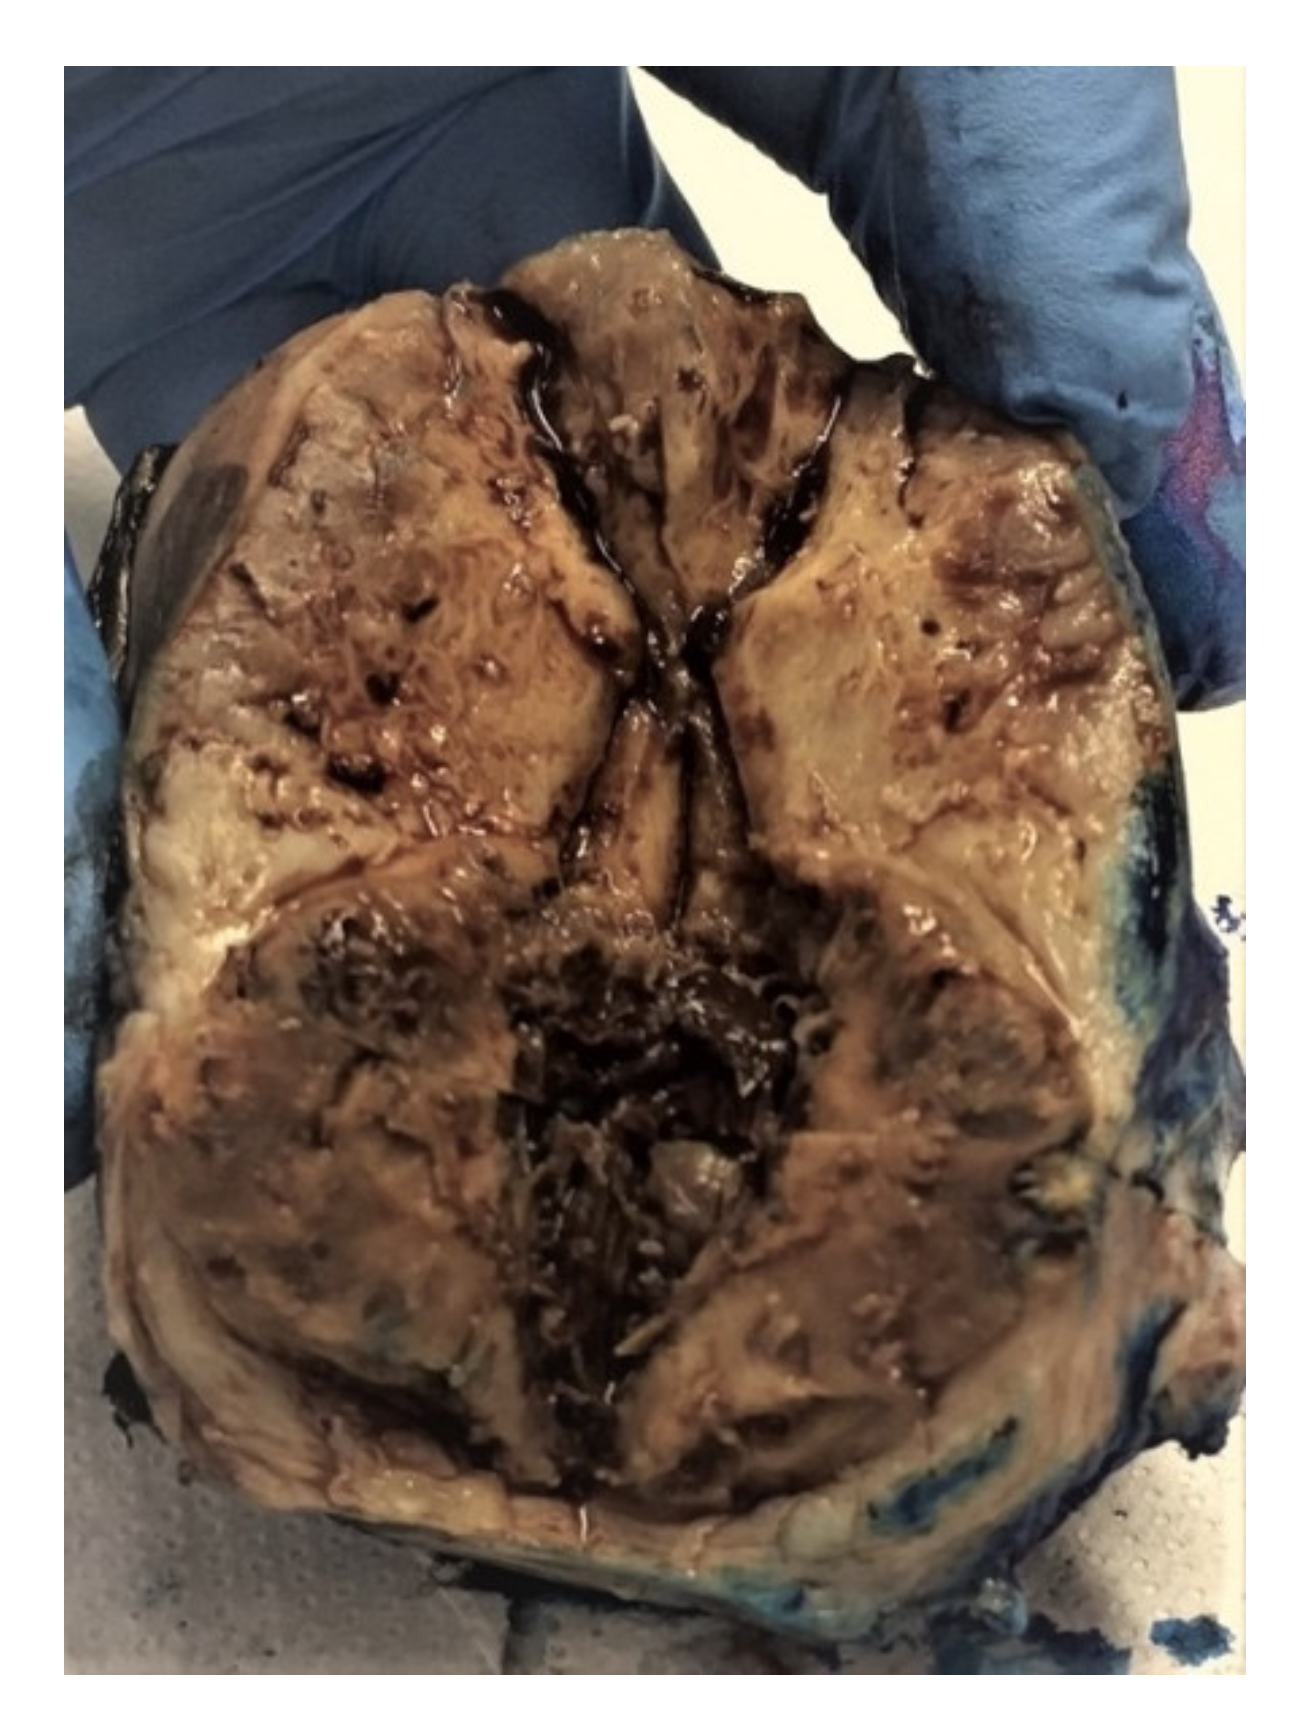

2.4.1. Macroscopic Features

2.7.1. Macroscopic Features